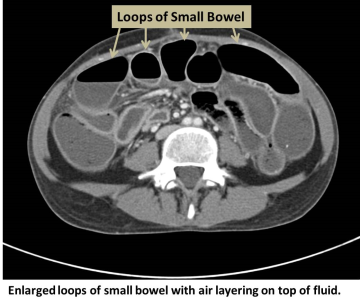

Enlarged loops of small bowel with air layering on top of fluid